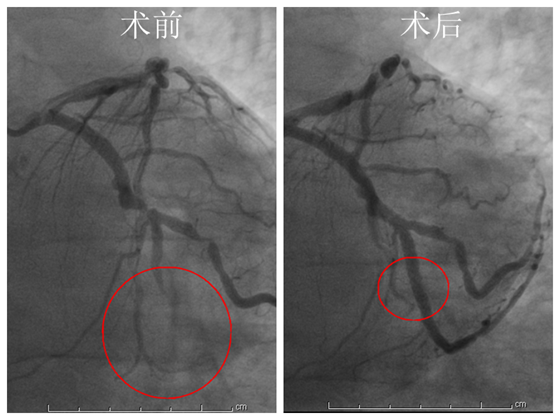

时间就是生命,心内科主任彭道地、范爱德副主任医师、龚辉医师、介入护士刘玲慧和刘秋蓉已准备就绪,患者被送入导管室。10:10,开始术前准备:心电监护、建立静脉通道……10:19,冠脉造影提示:前降支中远端弥漫性狭窄,回旋支近段狭窄99%、中远端完全闭塞。10:32球囊通过,罪犯血管血流恢复,患者立刻出现再灌注性心律失常,室速、室颤,马上除颤和抗心律失常药物治疗。医护团队迅速在回旋支病变处植入支架1枚,开通闭塞血管。但术后很快出现无复流、再次发生室颤,整个导管室开始紧张起来,彭道地主任及范爱德副主任医师凭借着多年的经验立即再次电除颤,并行冠脉内溶栓及补钾、补镁等积极治疗后,患者血压、心律逐渐恢复正常,胸痛消失。在导管室观察30分钟,患者的心电活动稳定,生命体征正常。11:10患者安返病房。